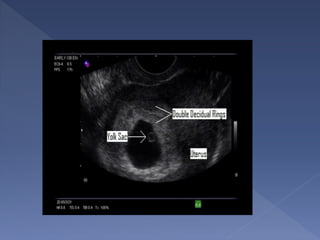

 presence of the double decidual sign

 Seen at 5 weeks

gestation

 Differentiates

true from pseudo

gestational sac

 Seen at 20 mm

sac diameter

abdominally and

8 mm sac

diameter

vaginally